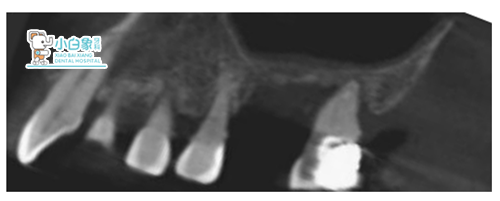

检查:口内查:16 二度松动,远中见白色充填物,探诊(-),叩诊(+),冷热诊正常,17 2度松动,探诊(-),叩诊(-),牙龈萎缩至根中三分之一,牙龈未见明显红肿,牙结石2度。

影像学检查:16 17见充填物影像。